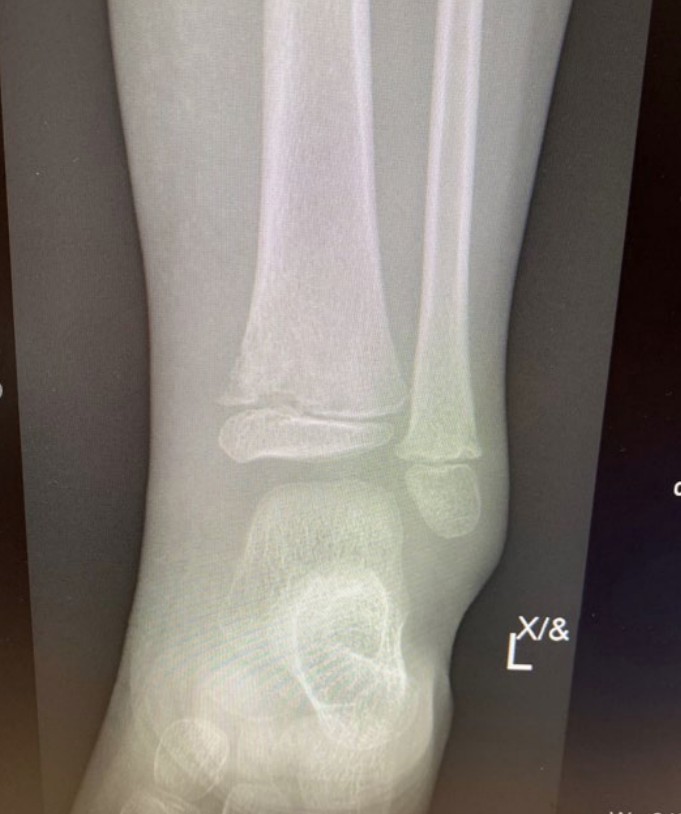

Non-accidental injury – metaphyseal fracture

A 3-month-old boy presents as unsettled. On examination he appears to have a painful leg and an X-ray is performed.

Toddler limp

A 2-year-old boy is brought to your ED not weight-bearing on his left leg for 5 days, progressively reluctant to …

Compartment syndrome

You are called to see patient in your department who is awaiting orthopaedic admission for a complex lower leg fracture …